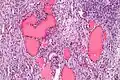

Higher magnification

| Micrograph of a struma ovarii. Characteristic thyroid follicles are seen on the right, and ovarian stroma on the left. H&E stain. | |

A struma ovarii (literally: goitre of the ovary) is a rare form of monodermal teratoma that contains mostly thyroid tissue, which may cause hyperthyroidism.[1]